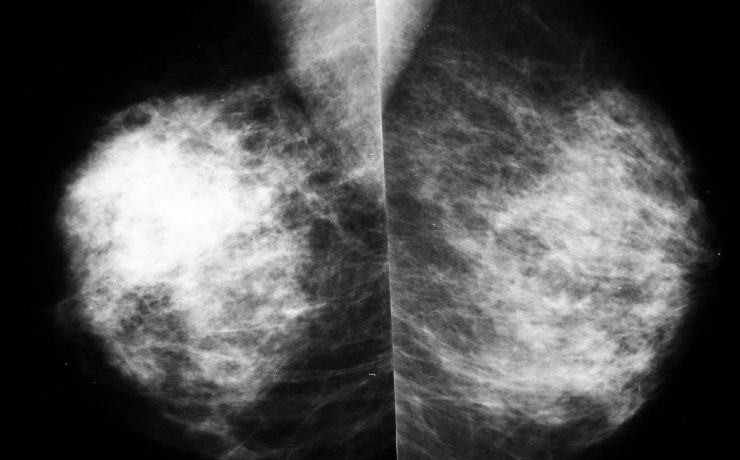

Caso clínico Se presenta un caso clínico de hematocervix diagnosticado por ultrasonografía en una paciente peri menopáusica sin antecedentes de patología cervical. Se discuten las causas de esta alteración, la utilidad del diagnóstico por ultrasonido, su tratamiento quirúrgico y su relación con patologías en otros órganos y sistemas. Introducción La